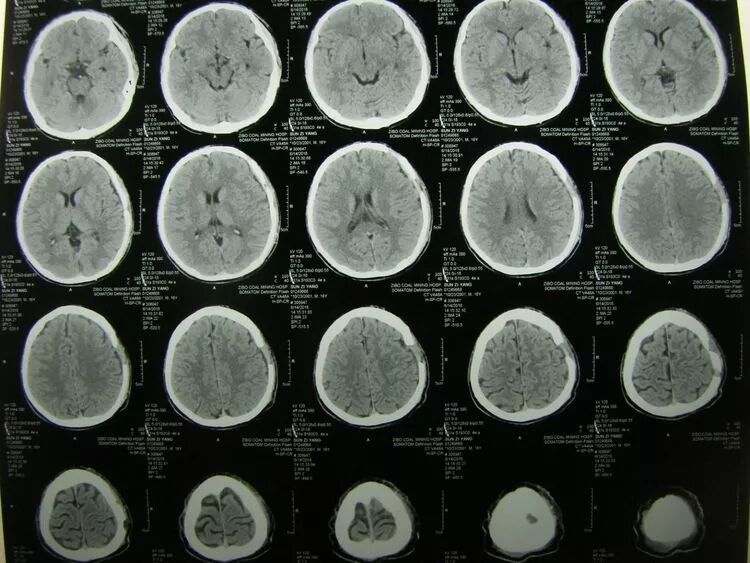

术后1天CT复查,血肿清除满意,未见迟发出血,患儿神志清醒。

术后2周CT复查,颅内未见迟发病灶,创口愈合良好,患儿己下床活动,拆线后出院。